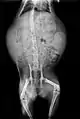

رادیوگرافی از شکم گربهٔ باردار